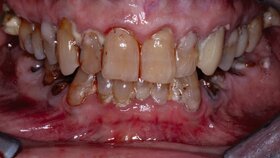

Zudem werden viele ältere Menschen wahrscheinlich mehr eigene Zähne besitzen und möglicherweise höhere Ansprüche bezüglich ihrer Mundgesundheit haben. Damit werden auch die Anforderungen an die Prävention und die therapeutischen Maßnahmen steigen. Auf den ersten Blick scheint es so, dass die zahnärztlichen Maßnahmen bei alten Menschen nicht signifikant von denen bei Jüngeren abweichen – im Detail ergeben sich aber durchaus Unterschiede bezüglich der Behandlungsmöglichkeiten und -maßnahmen: Mit zunehmendem Alter nimmt die Häufigkeit von Krankheiten zu, die zu Mundgesundheitsproblemen führen können. Es ändert sich die Sichtweise bezüglich der Inanspruchnahme zahnmedizinischer Leistungen und die subjektive Wahrnehmung korreliert häufig nicht mehr mit dem objektiven Befund. Außerdem gibt es immer mehr Menschen mit erheblichem Pflegebedarf. In dieser Patientengruppe ist der Karies-Sanierungsgrad wesentlich geringer als bei älteren Seniorinnen und Senioren, die keinen Pflegebedarf haben. Bei der Umsetzung von individuellen Präventionskonzepten ist neben der Etablierung einer altersgerechten Mundhygiene, der Anwendung von Fluoridpräparaten und dem Einsatz unterschiedlicher Biofilm-modifizierender Präparate einer Veränderung der Ernährungsgewohnheiten Aufmerksamkeit zu schenken.

Für die Praxis bedeuten diese Fakten, dass bei Seniorinnen und Senioren ein verstärktes Augenmerk auf Präventivmaßnahmen unter Berücksichtigung der Zunahme freiliegenden Wurzeldentins gerichtet werden muss. Zudem werden vermehrt Austauschrestaurationen erforderlich werden. Da bedingt durch den Abbau des parodontalen Stützgewebes Wurzelkaries-Läsionen zunehmen werden, müssen neue Restaurationskonzepte Eingang in die Praxis finden. Dabei sollte im hohen Alter und bei Patienten mit schlechtem Allgemeinzustand die Erneuerung von Restaurationen mit Augenmaß vorgenommen werden. Vermutlich wird also die Anzahl von Reparaturmaßnahmen zunehmen.